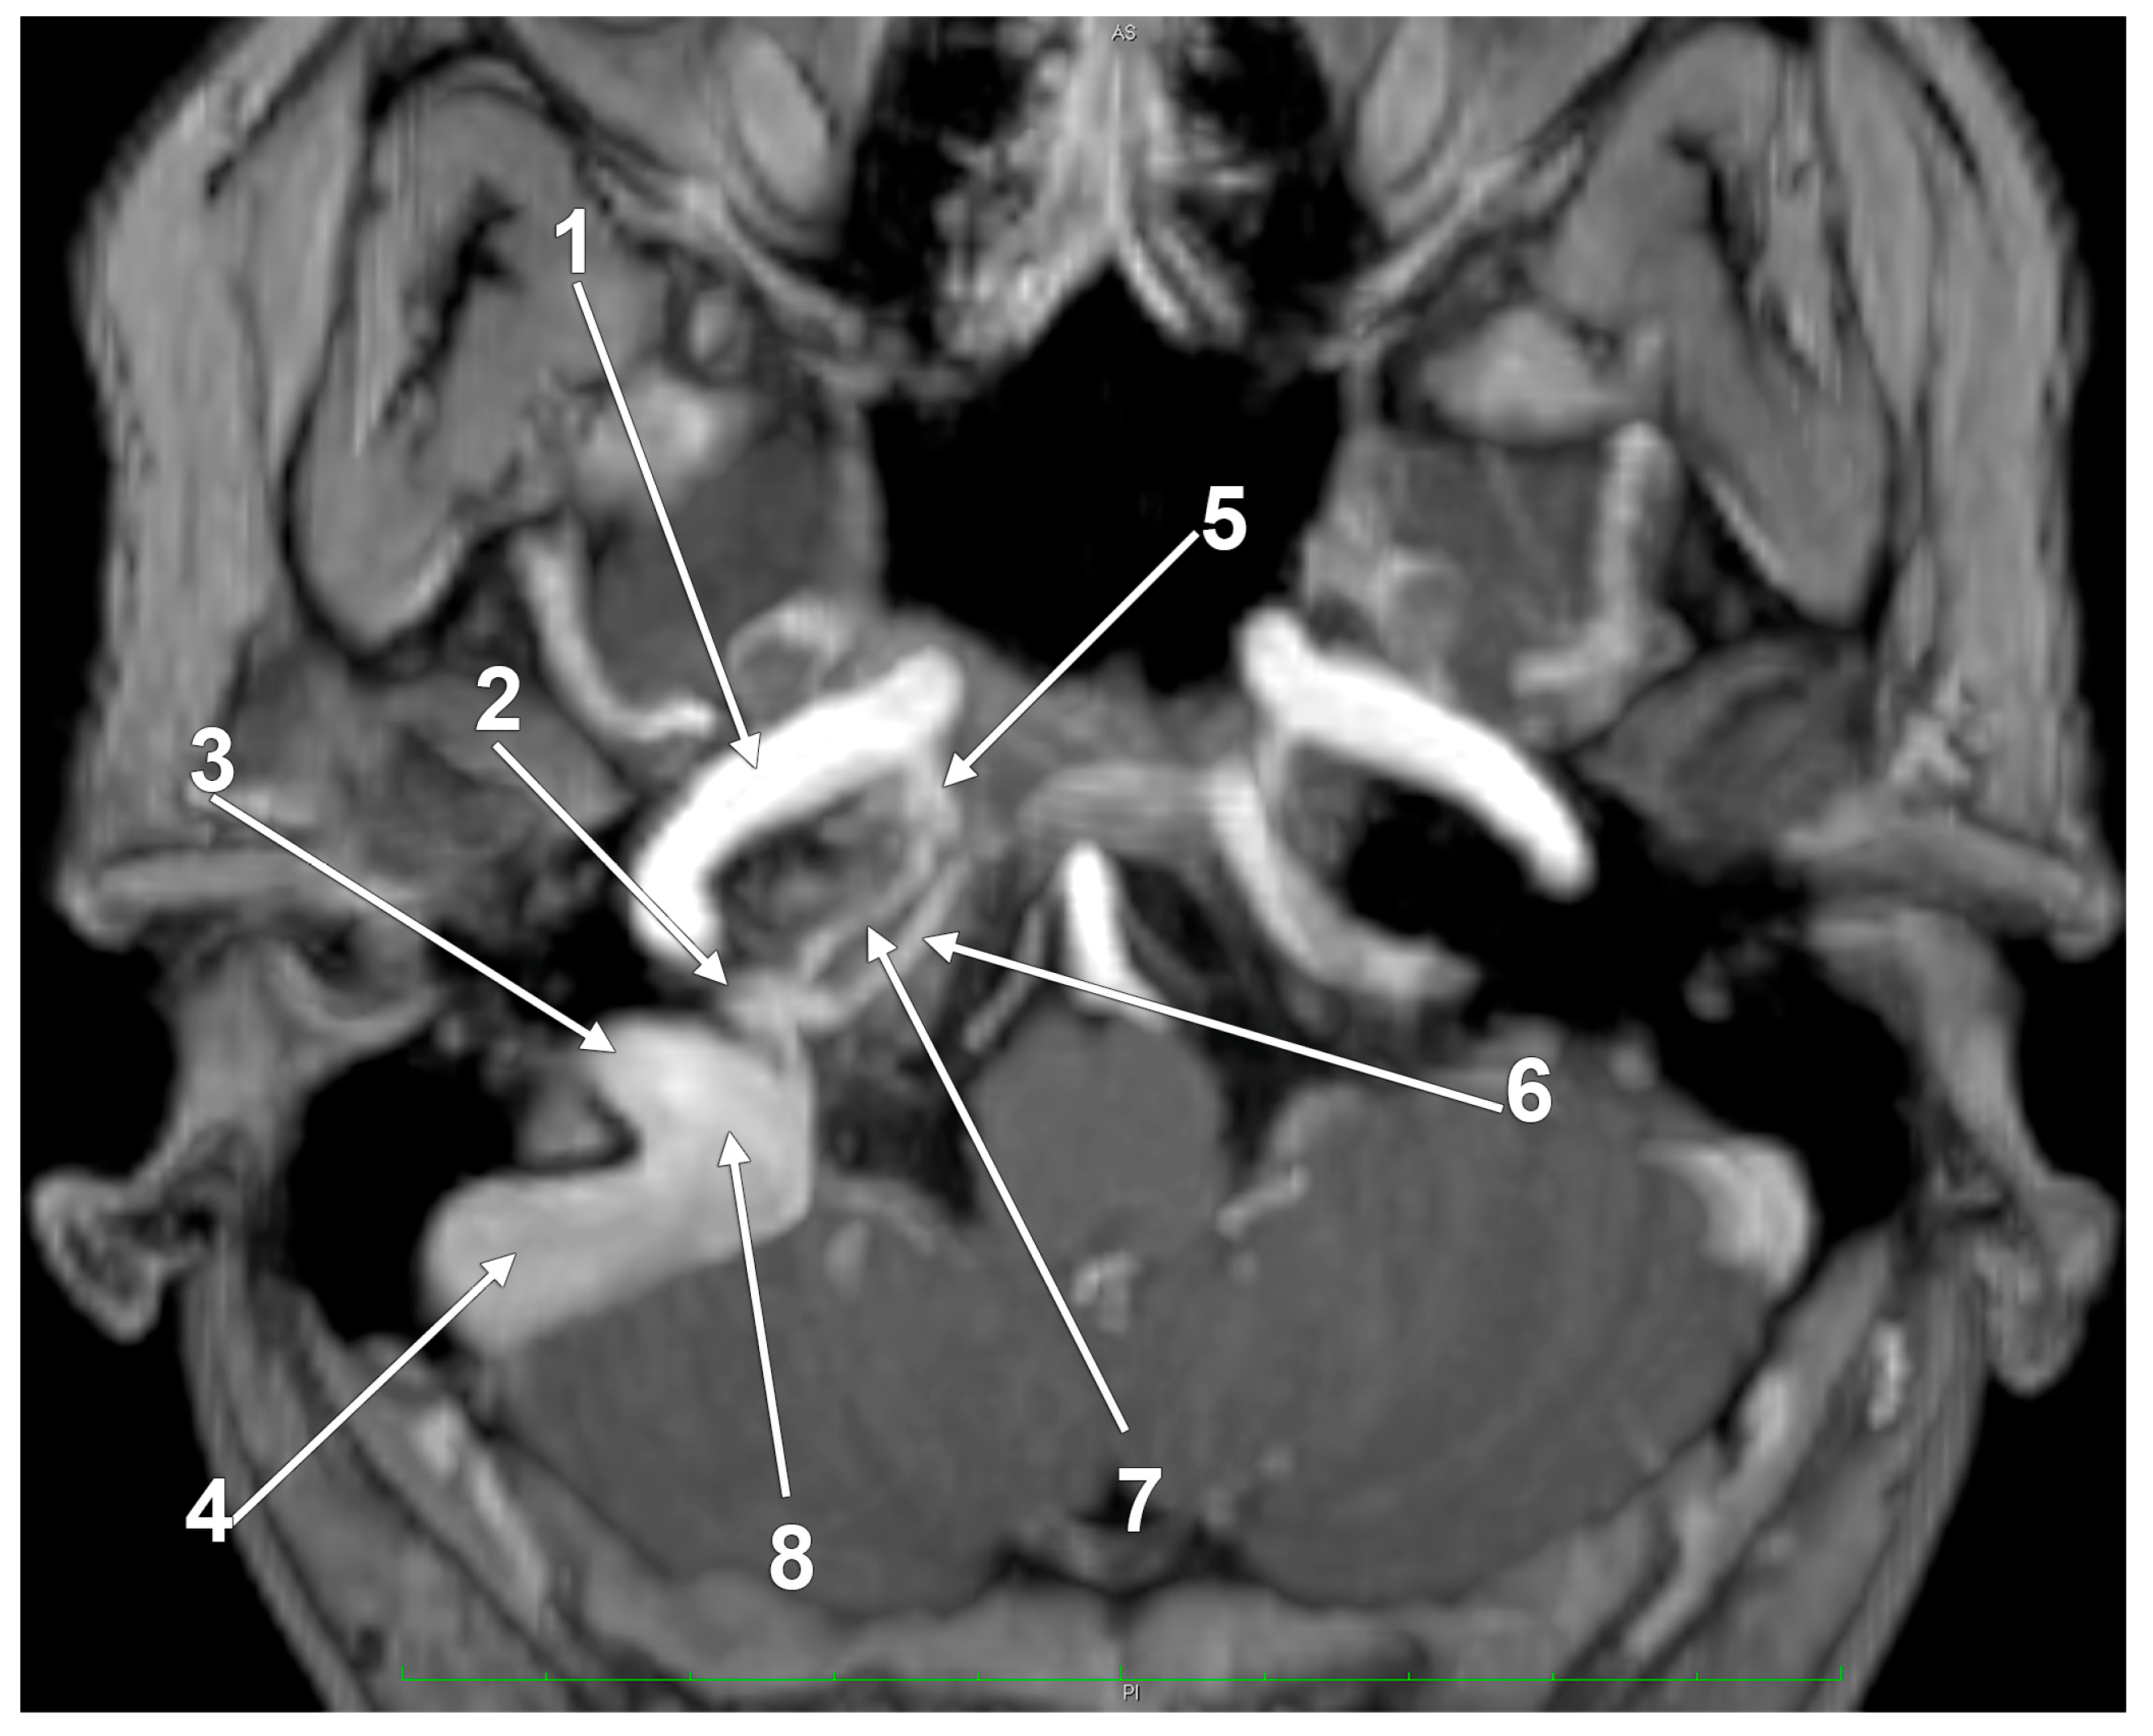

The “Condylar Jugular Diverticulum”: True or False?

- Raghuram, K.; Cure, J.K.; Harnsberger, H.R. Condylar jugular diverticulum. J. Comput. Assist. Tomogr. 2009, 33, 309–311. [Google Scholar] [CrossRef]

- Jagtap, R.; Wazzan, T.; Hansen, M.; Kashtwari, D. Condylar jugular diverticulum: A report of 3 cases. Imaging Sci. Dent. 2019, 49, 251–256. [Google Scholar] [CrossRef]

- Parillo, M.; Vaccarino, F.; Mallio, C.A.; Quattrocchi, C.C. Right Condylar Jugular Diverticulum: Contrast-enhanced Computed Tomography Findings of a Rare Anatomical Variant of Jugular Bulb. Indian J. Otolaryngol. Head Neck Surg. 2023, 75, 2257–2259. [Google Scholar] [CrossRef] [PubMed]